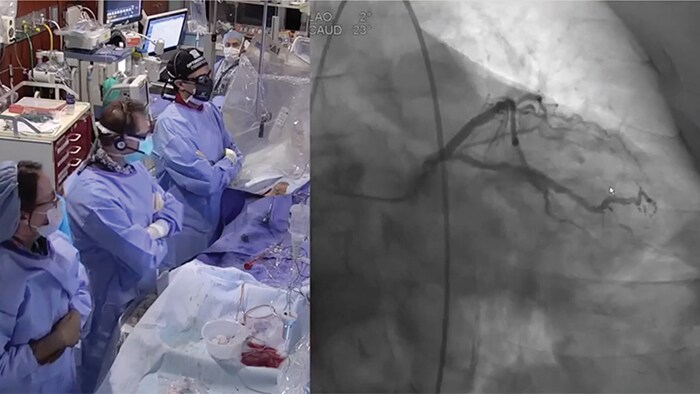

New invasive imaging techniques and co-registration software allows PCI to be performed with limited amounts of contrast, even with zero-contrast use, to reduce the risk of CI-AKI for all patients, and especially those with renal insufficiency.

Philips PCI guidance solutions incorporate non-invasive and adjunctive IVUS and iFR modalities, requiring less contrast for proper diagnosis.